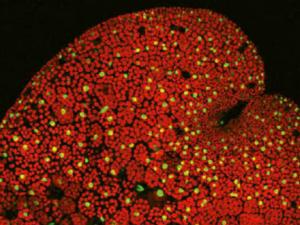

Un nuevo estudio en ratas revela el potencial de la resonancia magnética para detectar deficiencias en la conectividad cerebral antes de que aparezcan los primeros síntomas de la enfermedad de Alzheimer. Las imágenes se procesaron para obtener un mapa de la conectividad estructural y funcional del cerebro. Los resultados mostraron que en los animales enfermos había un retraso en la capacidad de aprendizaje.